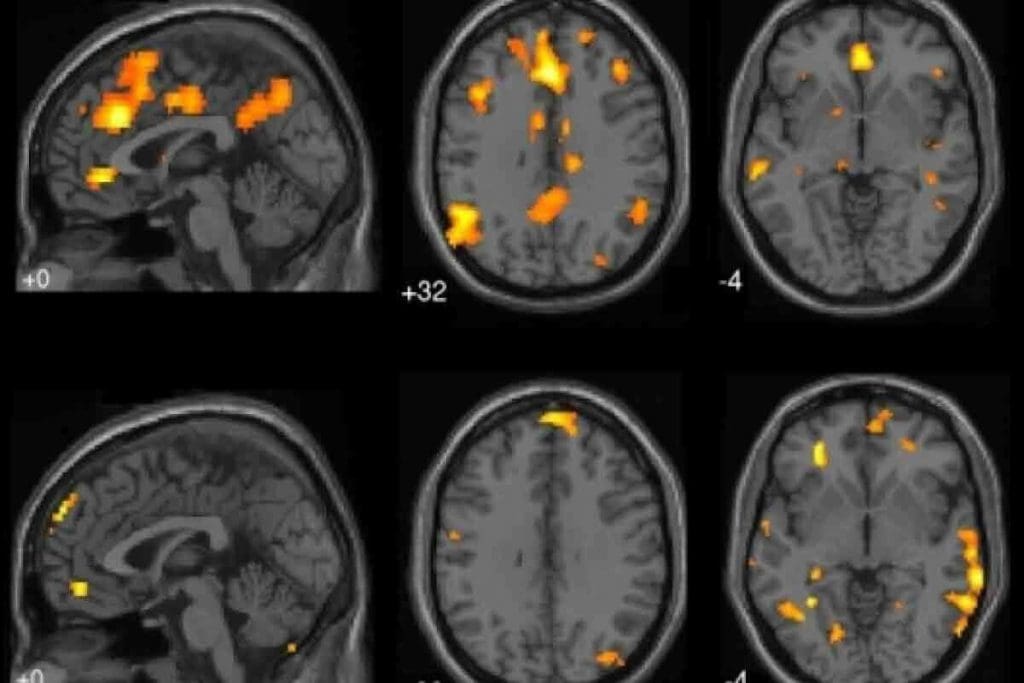

Computer Vision-Based Segmentation

Computer vision-based segmentation is another advanced method for brain tumor assessment. It uses artificial intelligence to make tumor identification more accurate and quicker.

“The integration of computer vision in medical imaging has the power to change how we diagnose, making it more precise and faster.”

Molecular Profiling Correlations

Linking CT scans with molecular profiles is key in brain tumor evaluation. This mix of imaging and genetics helps doctors understand tumors better and plan treatments.

The future of brain tumor diagnosis is combining advanced CT techniques with molecular profiling. This will lead to more personalized and effective treatments.